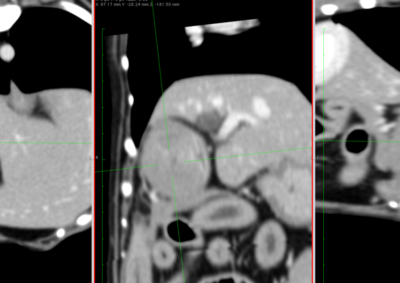

腫瘍外科 注意 ボタンをクリックした先に、治療中および手術中の画像が説明で使用されている場合がございます。 そのような画像に弱い方は閲覧なさらないようお願いいたします。 腫瘍外科 犬の甲状腺癌 軟部組織外科腫瘍外科 唾液腺癌 Salivary gland carcinoma 軟部組織外科腫瘍外科 胃部分切除術・ビルロートI 腫瘍外科 MLO 多小葉性骨腫瘍 腫瘍外科 軟部組織肉腫 G3 軟部組織外科腫瘍外科 直腸プルスルー 内科腫瘍外科 尾状葉乳頭突起に限局した高分化型肝細胞癌 内科腫瘍外科 猫の消化管型リンパ腫(腸穿孔を伴う) 腫瘍外科救急・集中治療 腹腔内出血 内科腫瘍外科救急・集中治療 細菌性腹膜炎 腫瘍外科 肝臓原発血管肉腫 腫瘍外科 犬の原発生肺癌(左) <1234567> 症例カテゴリー 放射線治療整形外科軟部組織外科脳神経外科内科腫瘍外科救急・集中治療リハビリテーション科腫瘍内科内視鏡科脳神経科呼吸器外科中医・漢方猫の腎移植循環器科